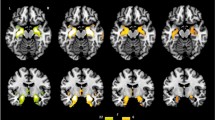

Cognitive performances, distribution of polygenic risk score for schizophrenia (PRS-SZ) and brain features associated with group-by-PRS-SZ interaction. A Performance on all studied domains for the cognitive subtypes. The cognitively spared group (CS, green squares) performed at a similar level compared to the healthy control group (HC, blue spheres), but the group with cognitive deficits (CD, red triangles) performed lower than both the HC and CD groups. B Distribution of the PRS-SZ among the cognitive subtypes. C Results from the moderation analyses following significant group-by-PRS-SZ interaction. (Left panel) When PRS-SZ was entered as the moderator, the CD group had larger precentral GMV than both the CS and HC groups, with the CS group showing larger precentral GMV than the HC group, only for those with low (diamond, steal dashed line) or average (circles, steal dotted line), but not high (brown star, dash-dotted line) levels of PRS-SZ. (Right panel) When groups were entered as moderators, decreased grey matter volume in the left precentral gyrus was associated with higher PRS-SZ in the CD group (red triangles), but not in CS (green squares) or in HC groups (blue circles). L: left; R: right; the colour-bar represents t statistics

In the absence of any significant direct effects of PRS-SZ or group on GMV assessed using whole-brain VBM analysis, the cognitive group-by-PRS interaction was significantly negatively associated with GMV in the left precentral gyrus (peak MNI coordinates [− 28, − 10.64], k = 47, t155 = − 5.25, z = 5.03, pFWE = 0.010; see Fig. 1C and Table 3 for statistics associated with this cluster). After extraction of the raw GMV at the cluster peak, the model testing the direct effects of PRS-SZ, group or their interaction on GMV was significant [R2 = 0.443, F(10,153) = 13.273, p < 0.001]. Within this model, the direct effect of group and the interaction effect were significant [R2 change = 0.117, F(2,153) = 16.791, p < 0.001], but not the direct effect of PRS-SZ.

The first moderation analysis testing PRS-SZ as the moderator of associations between cognitive subtype and GMV revealed that cases from the CD group at low and average, but not high PRS-SZ, showed significantly greater GMV in the left precentral cluster than both the HC and CS groups. Similarly, cases from the CS group with low and average, but not high PRS-SZ had significantly greater GMV in the left precentral cluster than the HC group.

The second moderation analysis testing ‘cognitive subgroup’ as the potential moderator of the relationships between PRS-SZ and GMV in the left precentral cluster revealed a negative relationship between PRS-SZ and grey matter in this cluster for the CD group only; the associations between PRS-SZ and GMV were not significant for the CS or the HC group (see Table 3).